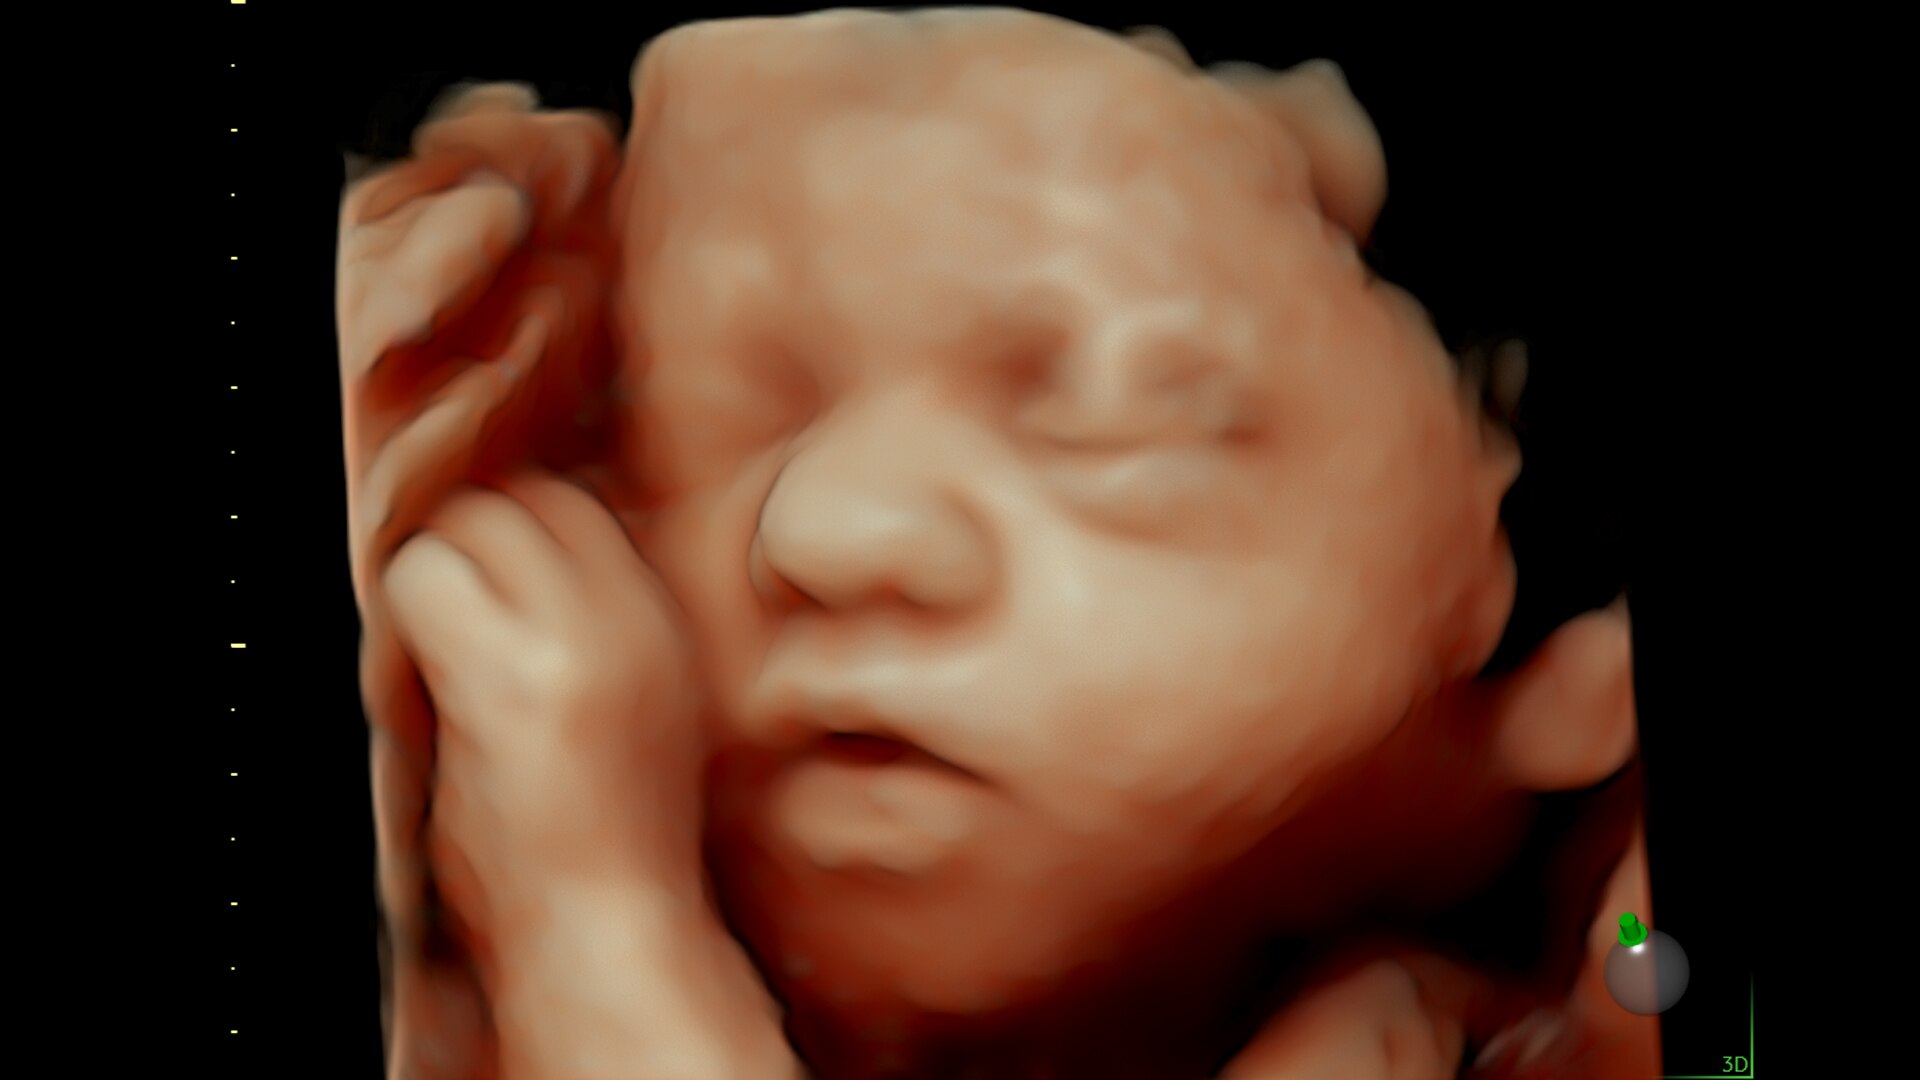

Advanced beamforming capabilities work in harmony with expert-level probes to deliver faster processing speeds and frame rates for enhanced detail and contrast resolution, greater color quality and sensitivity, and exceptional 3D/4D.

Fast, easy 3D-like blood flow visualization

Next level color Doppler delivers exceptional sensitivity for easy, fast visualization of blood flow, revealing even the tiniest vessels.

3-radiantflow-clinical-image